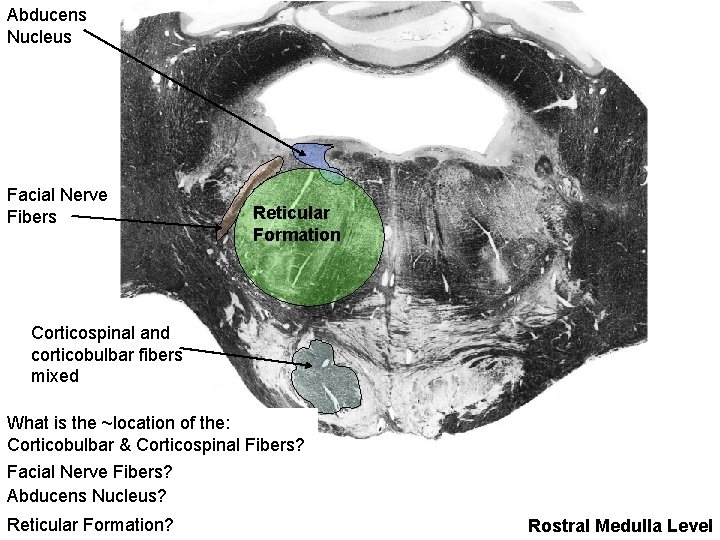

Abducens Nucleus Facial Nerve Fibers Reticular Formation Corticospinal and corticobulbar fibers mixed What is the ~location of the: Corticobulbar & Corticospinal Fibers? Facial Nerve Fibers? Abducens Nucleus? Reticular Formation? Rostral Medulla Level